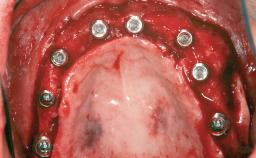

A 20-year-old woman was referred for implant therapy in 2004. Her medical history revealed no significant findings, and neither did she smoke nor take any medications. An extraoral examination revealed no abnormalities of the skin, hair or nails. The intraoral examination revealed only 11 permanent teeth clinically. These were normal in shape, size, and color. In addition, eight retained deciduous teeth (53, 62, 63, 71, 72, 73, 81, 82) were present. No abnormalities were detected during the general examination. The family history revealed that the patient’s father and two sisters were on record with similar conditions. The clinical examination revealed a thick gingival biotype. No recession of the attached gingiva was noted, but the retained deciduous teeth were mobile and unsightly. As a syndrome had not been diagnosed, the case was categorized as non-syndromic oligodontia.

| # of Implants | 12 |

| Type of Implants | One-Piece|Reduced-Diameter |

| Bone Augmentation | Horizontal|Staged |

| Augmentation Materials | Autogenous chips|Autogenous block(s)|Membrane |

| Bone Volume | Deficient horizontally, requiring prior grafting |